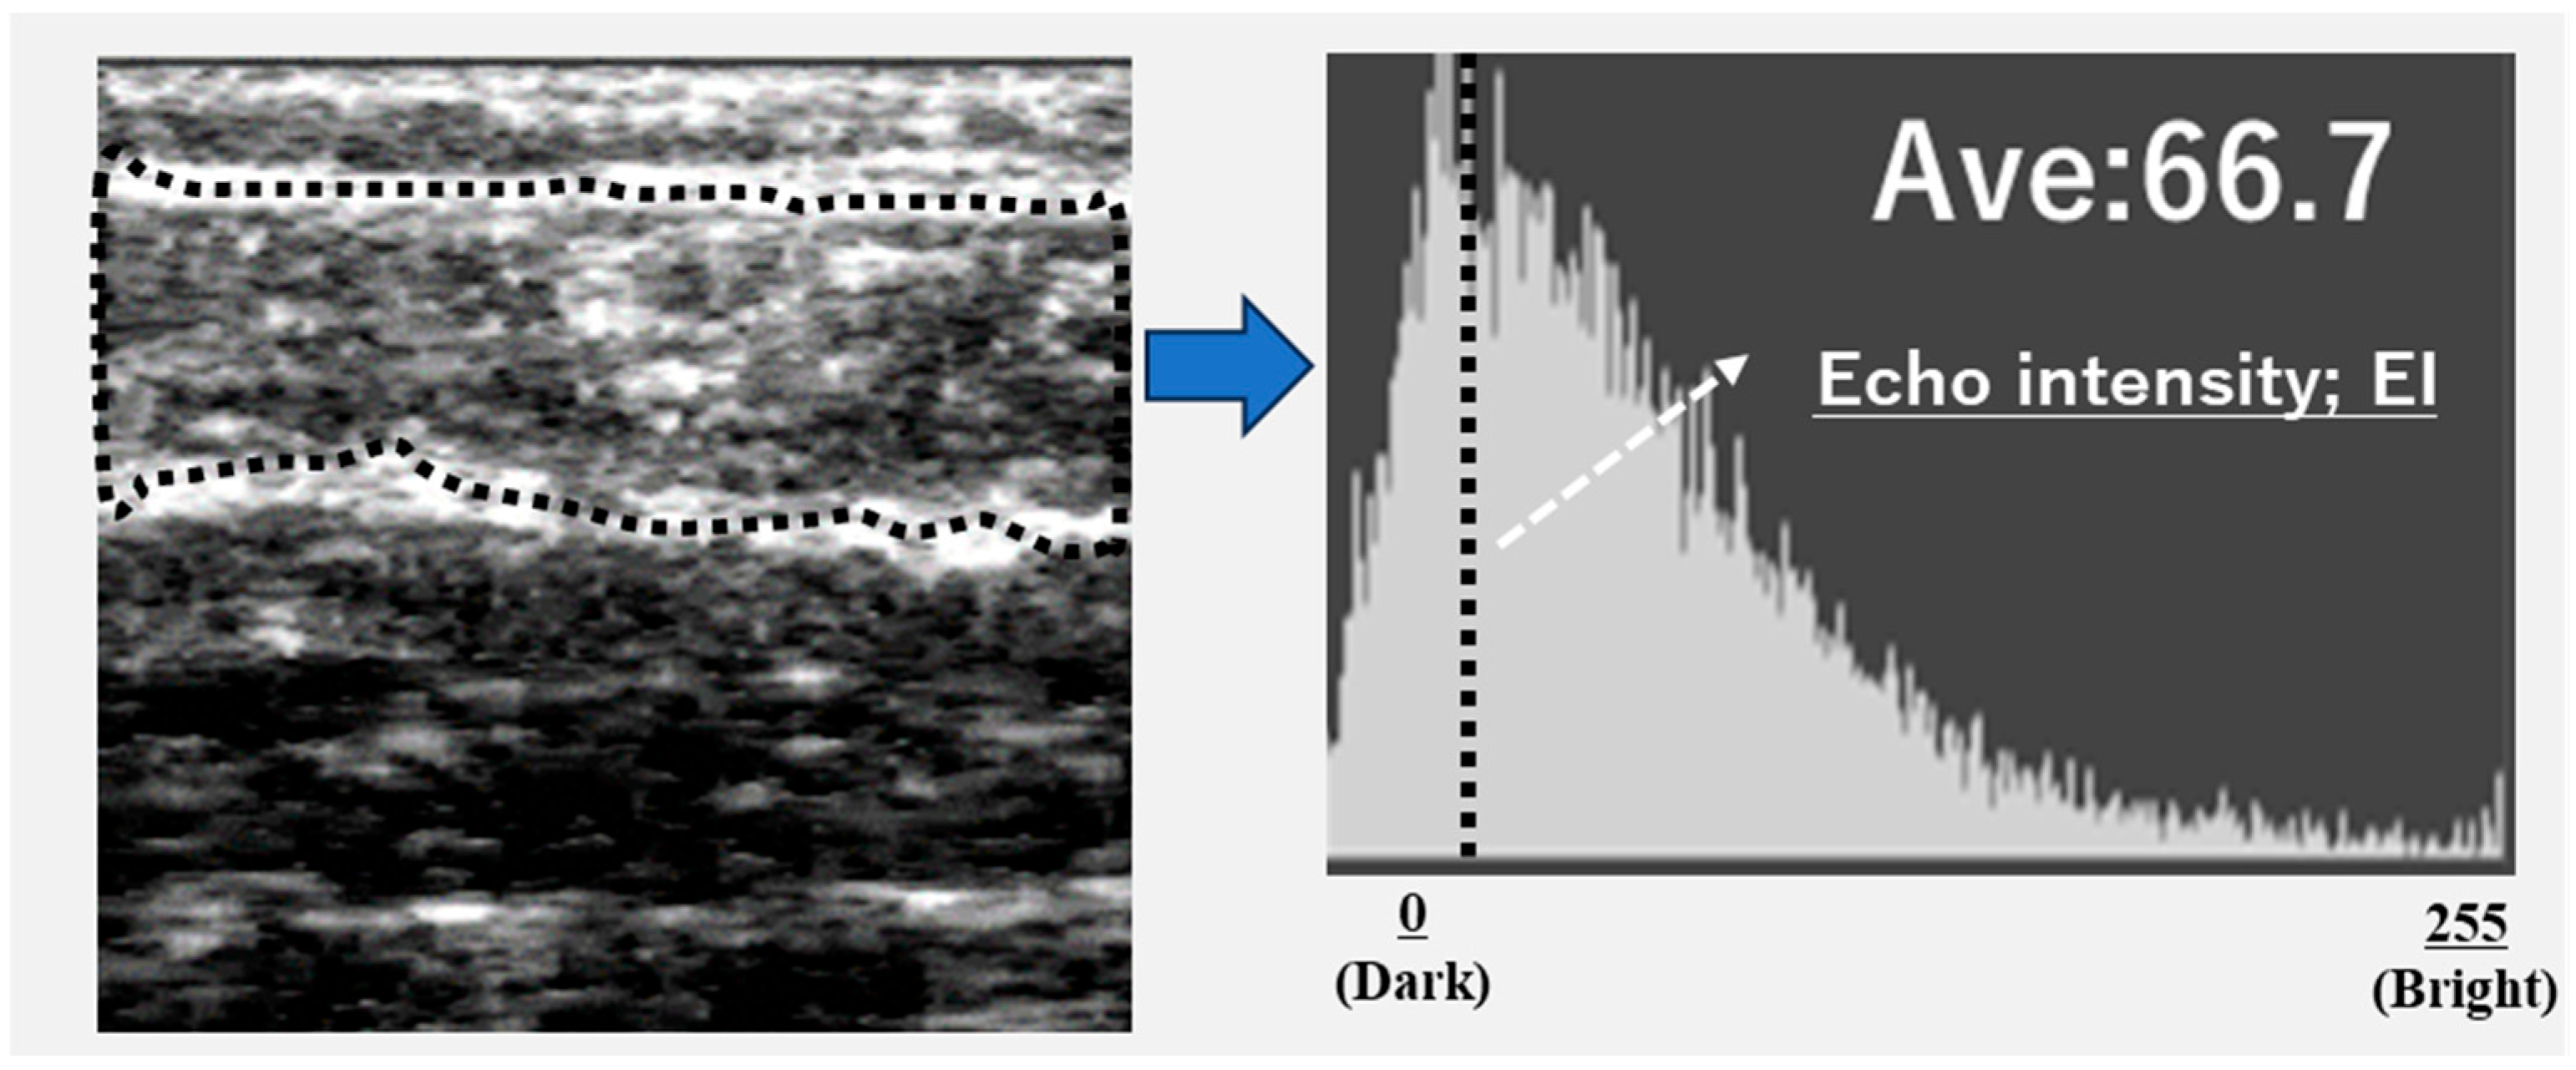

Ultrasound images were exported as Joint Photographic Experts Group (JPEG) files, and the EI of the gastrocnemius muscle was calculated using Adobe Photoshop Elements (Adobe Systems, Inc., San Jose, CA, USA). The target area was selected to include as much muscle tissue as possible while avoiding the surrounding fascia. The selected area was converted to an 8-bit grayscale image, with the mean image brightness presented as a value ranging from 0 (black) to 255 (white) (Figure 2). The EI was calculated as the mean image brightness [10]. This study analyzed the EI and GT of the leg with the lower ABI.

Figure 2. Calculation of echo intensity from the ultrasonographic image.